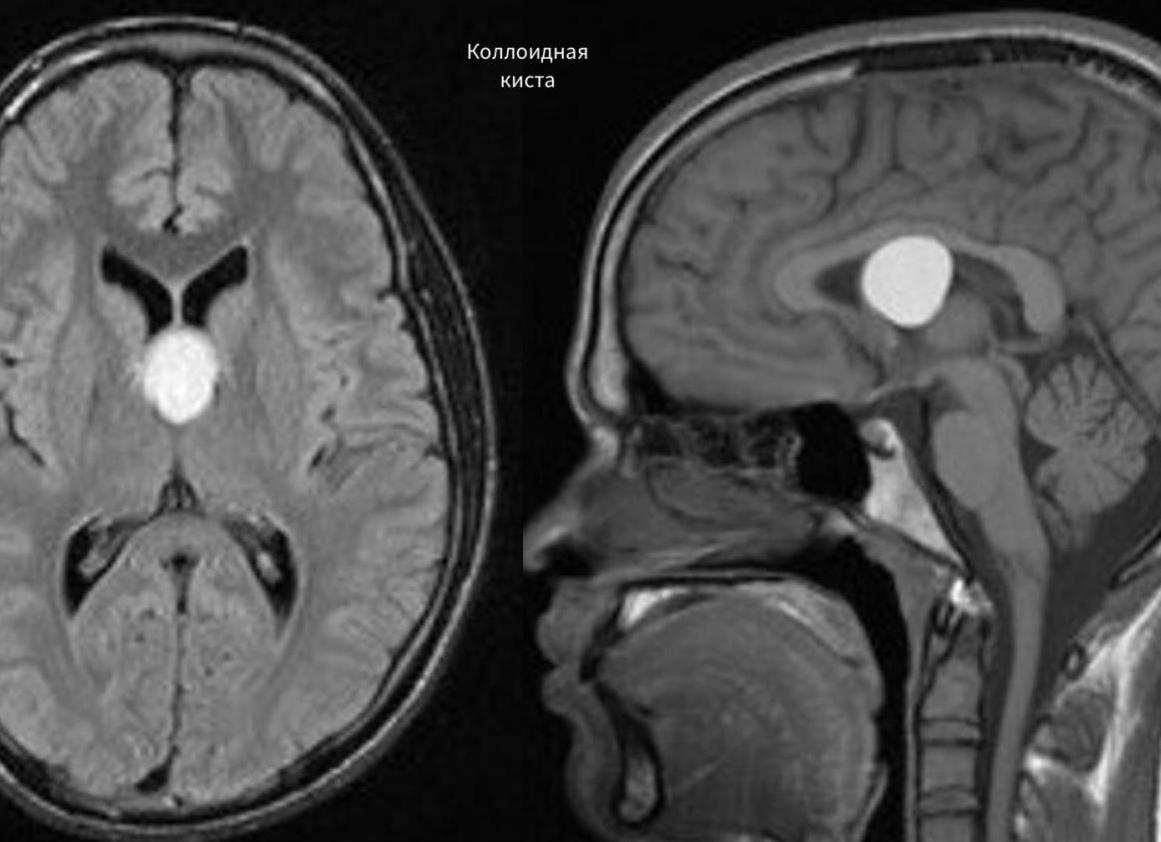

- Коллоидная киста возникает на стадии эмбрионального развития плода, когда формируется ЦНС. Чаще всего ее присутствие в организме не сопровождается ярко выраженной клинической картиной. Иногда киста влечет за собой нарушение тока ликвора. Это, в свою очередь, опасно гидроцефалией и летальным исходом.

- Коллоидальная киста головного мозга – кистозное образование, возникающее на стадии эмбрионального развития в процессе формирования центральной нервной системы плода. Коллоидальная киста может существовать бессимптомно на протяжении всей жизни пациента. Основным риском, возникающим при кисте головного мозга такого типа, является нарушение тока ликвора, что приводит к негативным последствиям (гидроцефалия, формирование мозговых грыж, смерть);